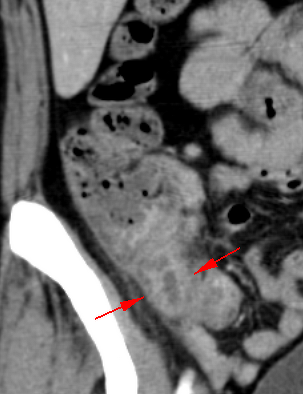

• CT検査